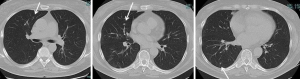

The sensitivity of helical computed tomography in the detection of CRC metastases ranged from 35.5% to 95.5%. Unilateral solitary lesions were found with additional malignant lesions in less than 5% (P=0.023) (Figure 1) and increasing numbers of metastases were associated with increasing numbers of additional undetected metastases (Figure 2), always (100%) when 4 or more lesions were present (13).

Using VATS approach requires the intraoperative identification of the nodules by visualization, fingertip palpation (Figure 1) or with a touch-bar. This is not always successful.

VATS has an increasingly important role in lung metastases surgery. Minimally invasive approach allows enhanced recovery protocols and is associated with less pain, less complications, better functional outcome and shorter hospital length of stay. Its usefulness however, is limited when multiple or deeper parenchymal lesions have to be resected (Figure 2). Pulmonary metastasectomy by open thoracotomy is the standard procedure for 2 or more ipsilateral lesions, allowing manual palpation of the entire lung and thereby identifying additional undetected lesions. VATS approach is an alternative in special situations and should be preceded by a detailed radiological evaluation and when available using techniques such as MIP and CAD to increase detection sensitivity.